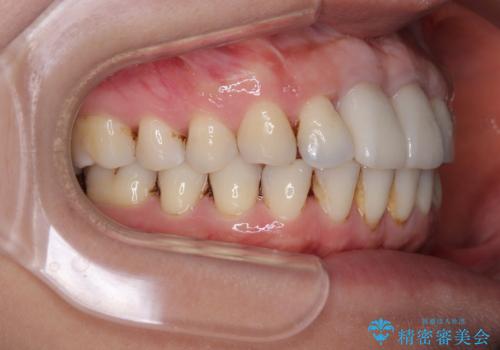

隙間をセラミックで閉じたら不格好で歯肉から出血 矯正治療と歯周外科で綺麗な前歯に

不適合なクラウンが装着されていたため、歯周ポケットが深くなっていましたので、矯正治療前に歯周外科処置を行って歯周ポケットを除去し、矯正治療後にオールセラミッククラウンにて補綴治療を行うこととしました。

前歯の見た目はもちろん、出血や腫脹のない健全な前歯の状態を獲得することができました。